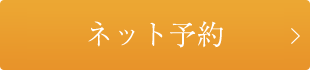

大きな病変があります。

なんとなく側枝が怪しそうですね。

ピンぼけしてます笑

作業長を決定し、